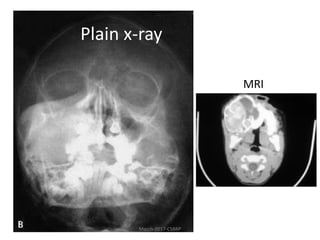

Case-3

• 5yo, African girl

with rapidly

growing jaw

swelling of

2months duration

Plain x-ray

MRI

• Describe the clinical image

• What do your think of x-ray findings? Is it

malignant or benign?